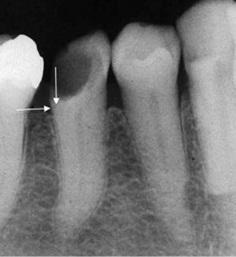

Restorative Treatments for Lesions with Subgingival Margins

Various approaches have been proposed for clinical cases where the margins of the cavity are subgingival.

- When asked about an emerging technique to restore the tooth called coronal marginal relocation (CMR), deep margin elevation (DME) or Proximal Box Elevation (PBE), about half of the practitioners have heard of (25%) or used the restorative technique (28%), but most were not aware of it (48%).